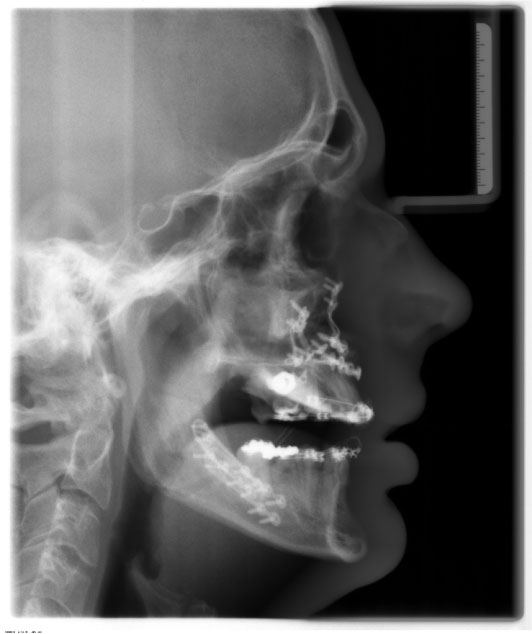

Figure 9: Cephalometric X-ray (lateral view) after bimaxillary osteotomy and bone augmentation. View Figure 9

After 6 months of healing, the implants could be revealed and individual gingiva formers were incorporated to shape the soft tissue (Figure 11).After additional three months, the final prosthetic device of high esthetic standard could be incorporated: Circonia for the maxilla and SiO2 ceramics for the mandible (Figure 12, Figure 13, Figure 14 and Figure 15).